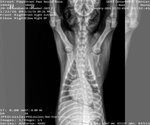

Dog Breed: German Shepherd Dog / Doberman Pinscher (medium coat). Adoption Fee: 400. Roxy is a goofy, silly girl with a huge heart and an even bigger love for life. All she really wants is someone to love her and a buddy to play with—she’s happiest when she’s being her playful, joyful self. Her story hasn’t been an easy one. Roxy was found on the side of the road in the rain after being hit by a vehicle, suffering multiple serious injuries including a broken shoulder, tail, femur, and even a break in her back. Thanks to the incredible team at Auburn University, she received life-saving surgery and care—and today, she’s doing amazingly well. Because of what she’s been through, Roxy does have some lingering PTSD, but she continues to grow more confident every day. She’ll need a patient, understanding home that will support her as she continues to heal and thrive, especially as she gets older. Roxy absolutely loves people and is wonderful with kids, though she can be a bit jumpy when she gets excited, so a home without very small children would be best. She also loves cats… unfortunately, the feeling isn’t always mutual. She would truly shine in a home with another friendly, playful dog who can be her companion. Due to her injuries and breed, Roxy cannot be spayed until she is at least one year old to allow her body to grow as strong as possible. Her future family will need to provide proof of spay when the time comes. Roxy has been through so much, but she hasn’t let it dim her spirit. She’s resilient, loving, and ready to find a home that will cherish her just as much as she’ll cherish them. Adoptions are limited to an approximately 150-mile radius from Locust Grove, GA, certain circumstances may allow exceptions. To apply to adopt this pet, please fill out a Preliminary Adoption Application at .streetpaws/adopt. T his application does not commit you to an adoption. It is used to screen those interested to make sure the home is a good match for the pet and your family. We verify vet history on current/previous pets to ensure pets have been spayed/neutered and vaccinated annually. Please call your vet to give permission for us to call them. Our adoption fee is $400 . She has been given age-appropriate vaccinations, receives monthly heartworm prevention, dewormed, receives flea prevention, and will be micro-chipped. We will ensure the microchip is registered. If more information is needed regarding the pet email infostreetpaws. You must complete the pre-application to obtain approval to meet the pet.